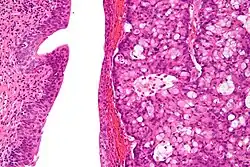

| Micrograph of urachal carcinoma (right of image) and non-malignant urothelium (left of image). H&E stain. | |

Urachal cancer usually is an adenocarcinoma (about 90%) mostly with mucinous/colloidal histology. Other rare types include urothelial carcinoma, squamous cell carcinoma, neuroendocrine carcinoma and sarcoma.[2][4][7][8]